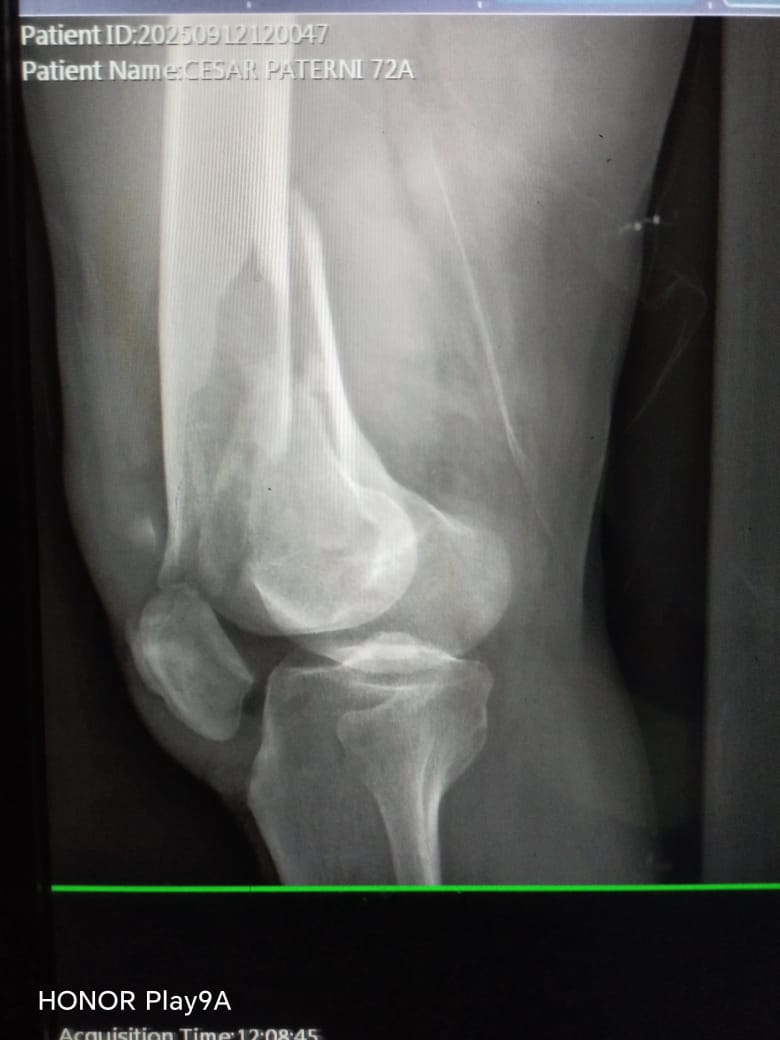

César Paternina, de 74 años, sufrió una caída el pasado 12 de septiembre que le ocasionó una fractura en el fémur, es decir, una rotura en el hueso del muslo, considerado el más largo y resistente del cuerpo humano.